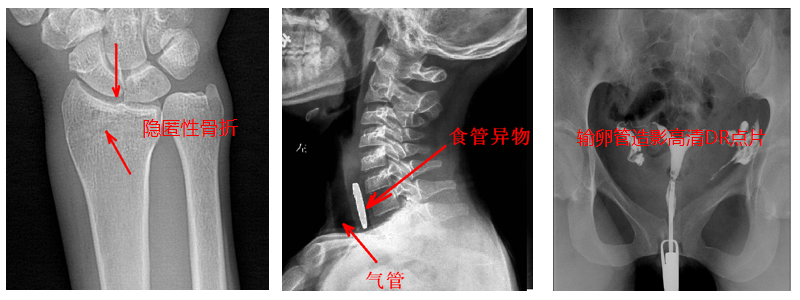

5.準(zhǔn)確點片。在透視下準(zhǔn)確找到病灶部位,這對于早發(fā)現(xiàn)隱匿性骨折有著不可替代的作用。更難能可貴的是,它可以在透視情況下進(jìn)行整骨復(fù)位以及術(shù)后在透視下檢查。

4.?dāng)?shù)字造影。PLD5500B動態(tài)DR機適用于各種普通及特殊造影,如口服膽囊造影、靜脈膽道造影、T管造影、逆行胰膽管造影(ERCP)、靜脈腎盂造影(IVP)、子宮輸卵管造影、脊髓造影等,主要應(yīng)用于消化內(nèi)外科、泌尿外科、婦科、神經(jīng)內(nèi)外科等。

2.?dāng)?shù)字透視。適用于全身各部位透視(如胸透、腹透等),以及在透視下DR點片等;動態(tài)采集速度≥25幀/秒,應(yīng)用于消化科、泌尿科、婦科等。